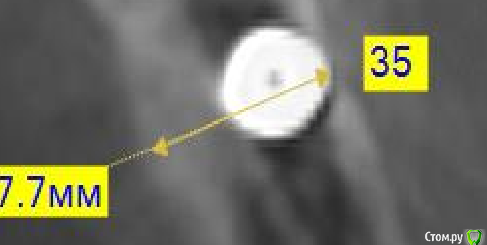

an_ver Опубликовано 11 января, 2016 Поделиться Опубликовано 11 января, 2016 Платформу нужно было язычно завалить чуть 4 Ссылка на комментарий

Stinjj Опубликовано 11 января, 2016 Автор Поделиться Опубликовано 11 января, 2016 (изменено) По-моему даже не чуть. чем чревато? Картикалка целая? Изменено 11 января, 2016 пользователем Stinjj Ссылка на комментарий

Tari Опубликовано 11 января, 2016 Поделиться Опубликовано 11 января, 2016 По-моему даже не чуть. чем ччревато? Картикалка целая?на кт нет антагониста сверху, а так если винтовая фиксация коронки, то шахта может выходить на вестибул. сторону, но, думаю, можно решить... 1 Ссылка на комментарий

Stinjj Опубликовано 11 января, 2016 Автор Поделиться Опубликовано 11 января, 2016 думаю может переделать пока свежий имплант?что про картикалку скажете - мне кажется размыты или я не очень умею читать 3D Ссылка на комментарий